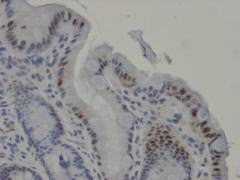

世界初の報告

世界初、私が米国で報告したバレット食道におけるCDX2の免疫染色写真(逆流性食道炎が長くつづくとバレット食道になります)

私は、「逆流性食道炎が長い期間治療されずに続くと、バレット上皮という上皮が出現してきて、これが食道の腺がんの発生母地になる。このバレット上皮の出現にはCDX2遺伝子が大きく関与する」ということを米国消化器病学会で発表しました。

この私の発表をもとに、フランスの医師、Marta Marchetti らが、「Chronic acid exposure leads to activation of the cdx2 intestinal homeobox gene in a long-term culture of mouse esophageal keratinocytes 」という論文を書いて、細胞レベルで確認してくれました。